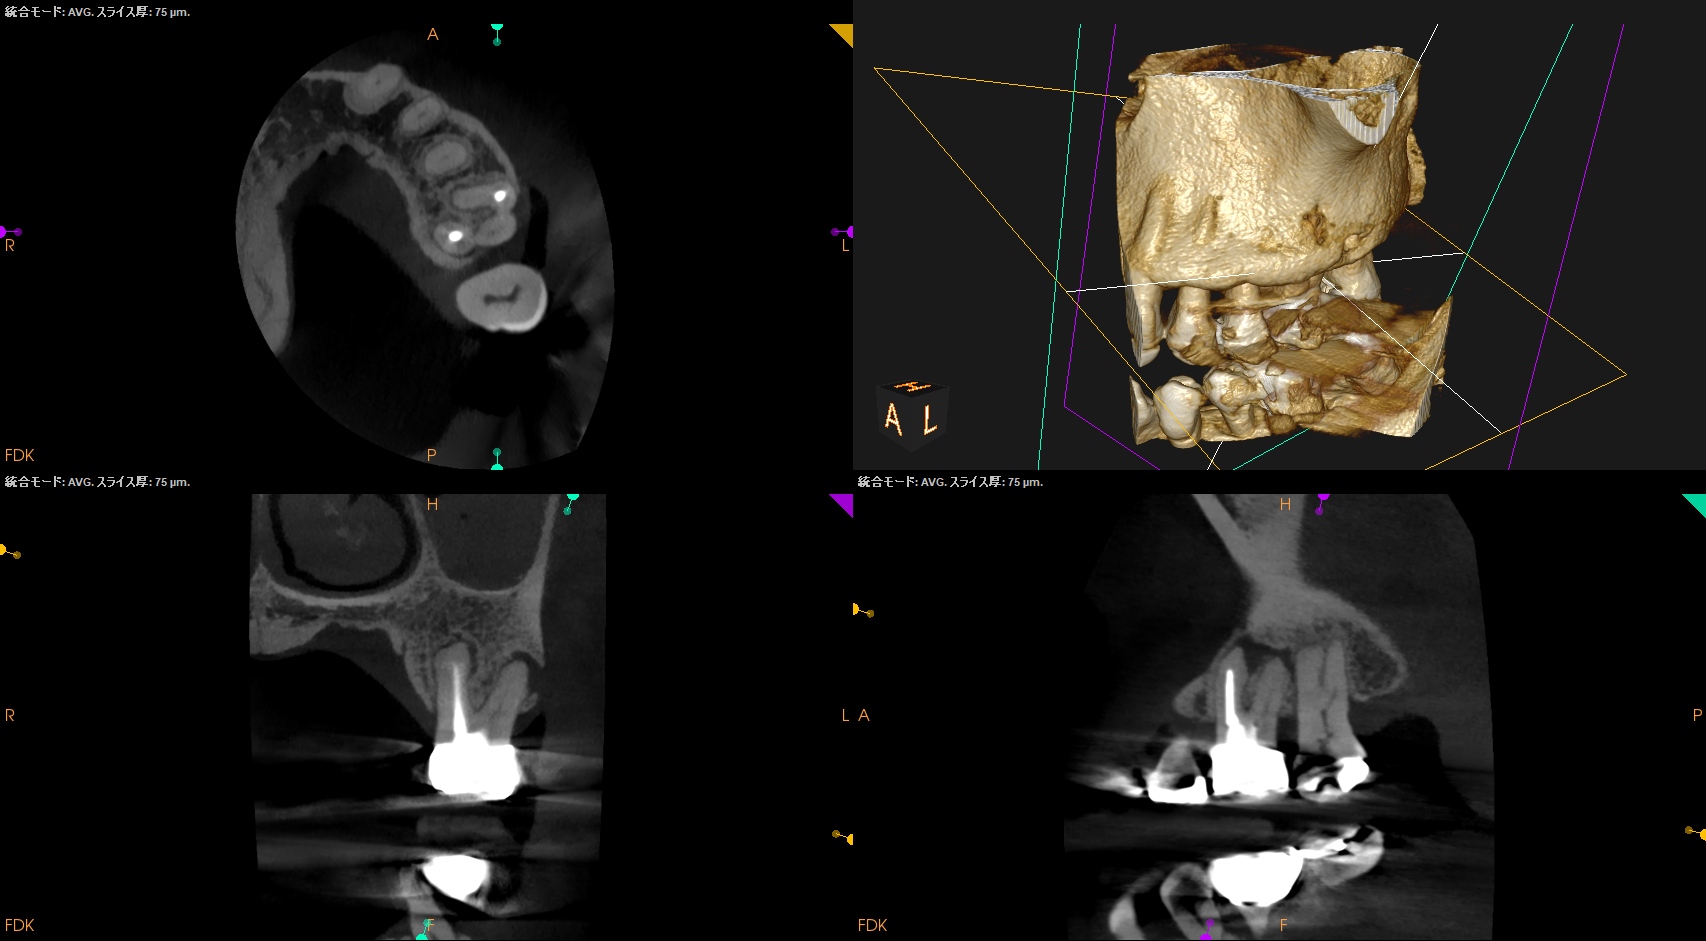

MB,DBは外科時には以下のようになる。

DBは楽だが、MBは頬舌径が7.4mmでMB1, MB2があるという…難ケースだ。

逆根充後にPA, CBCTを撮影した。

MB

DB

P

B